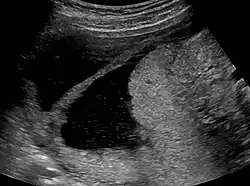

![]() | |

| Ultrasound view. | |

The history of a pregnancy event followed by a D&C leading to secondary amenorrhea or hypomenorrhea is typical. Hysteroscopy is the gold standard for diagnosis.[18] Imaging by sonohysterography or hysterosalpingography will reveal the extent of the scar formation. Ultrasound is not a reliable method of diagnosing Asherman's Syndrome. Hormone studies show normal levels consistent with reproductive function.